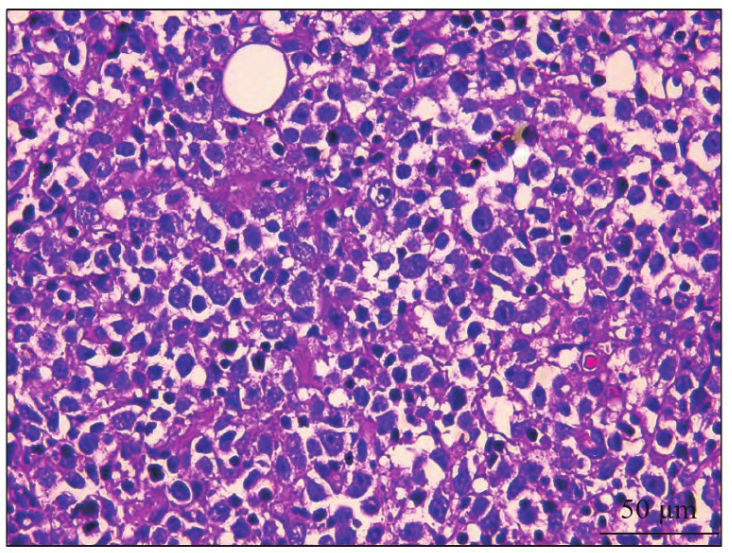

局部麻醉下取活检,苏木精-伊红(hematoxy-lin-eosin,HE)染色镜下见黏膜鳞状上皮内及下中等大至大的肿瘤淋巴细胞弥漫性生长(图1),胞质少,胞质嗜碱性、双嗜性,细胞核为卵圆形、圆形,有2~4个核仁贴近核膜,呈中心母细胞样细胞;免疫组织化学示肿瘤细胞CD20、B细胞特异性激活蛋白(paired box protein pax-5,PAX-5)、CD79a均弥漫阳性,Ki-67增殖指数约90%,CD10(图2)、Bcl-6、多发性骨髓瘤致癌蛋白(multiple myeloma oncogene 1,MUM-1)均阳性,呈生发中心B细胞型(germinal center B-cell,GCB),细胞角蛋白(cytokeratin,CK)、CD3、CD5、CD-30、CD138、周期素D1 (Cyclin D1)均阴性;荧光原位杂交技术(fluorescence in situ hybridzation,FISH)检测组织中骨髓细胞瘤病毒癌基因(cellu-lar-myelocytomatosis viral oncogene,c-MYC)表达(图3):肿瘤细胞内存在2个黄色信号或2个紧密相邻的红绿信号,提示c-MYC基因未发生断裂。

图1 病例1的HE染色图×100。